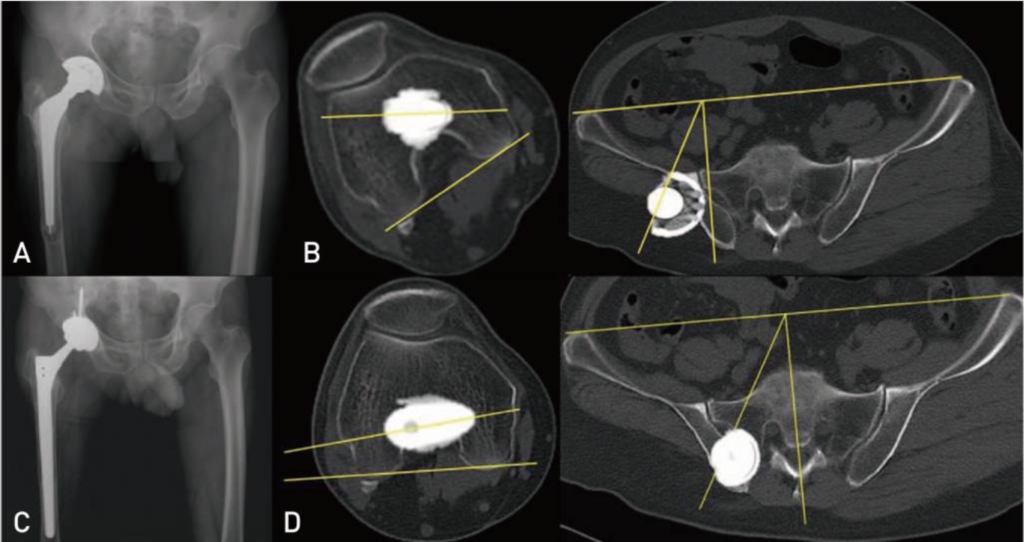

Диагностика ТБС рентгеном и асептический некроз: особенности лечения

Раздел: Снимки-откровения